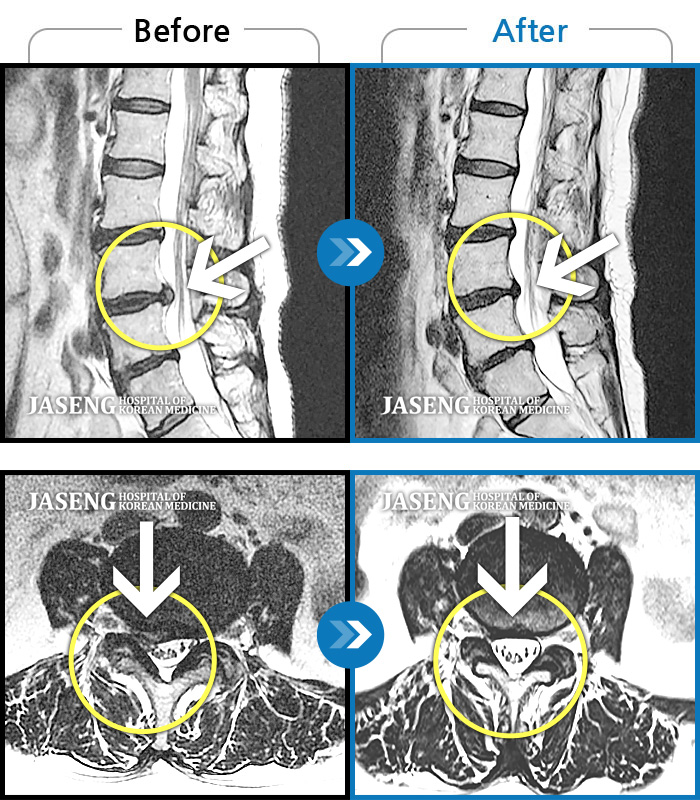

MRI 치료사례

누워서 잘 때나 서 있을 때 통증, 우측 골반 허벅지 통증